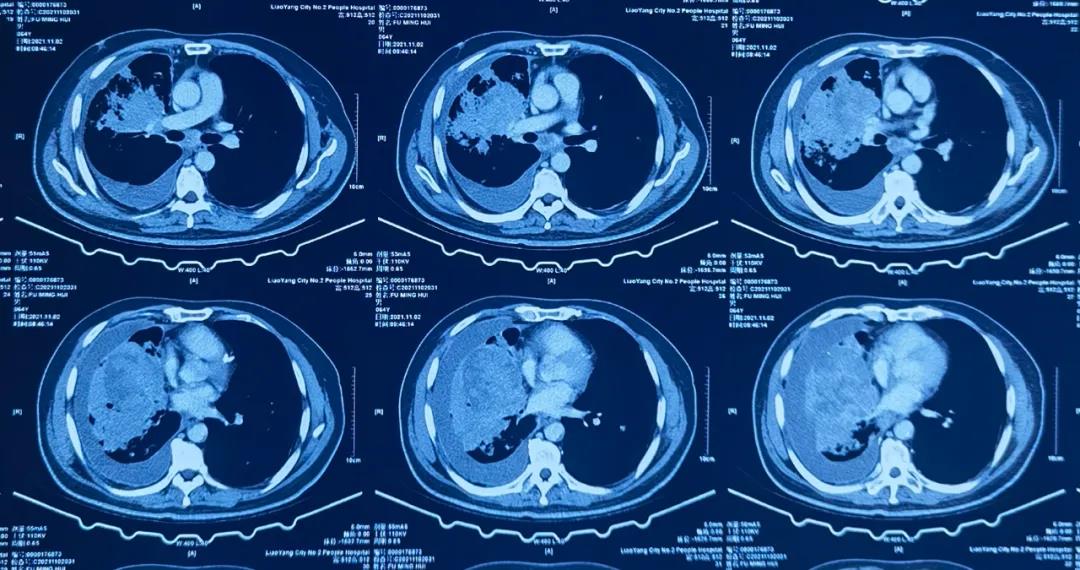

11月3日,我院呼吸一科主任李文杰在CT室、肿瘤治疗中心的密切配合下,成功为一名肺肿瘤患者完成“CT引导下经皮穿刺肺活检术”。

该患男性,咳嗽、咯血3个月,在其他医院检查发现右肺中叶占位性病变,右侧胸腔积液,肿物巨大,无法手术,为指导下一步治疗,急需病理结果,家属为此焦急万分,慕名来到我院求助。

李文杰主任认真分析患者病情,与CT室和肿瘤治疗中心共同研究探讨,认为CT下穿刺取病理可行,并以最快的时间成功实施活检术。此次穿刺活检术的成功,为该患进一步治疗提供了有利依据,家属多次流泪鞠躬表达对我院快速诊断的感激之情。

我院在辽阳地区开展肺、肝等活检术十余年,技术娴熟,为众多肿瘤患者解除了确诊难题。为解决肺小结节患者手术创伤的痛苦,医院还开展了微创手术微波消融治疗肺结节。